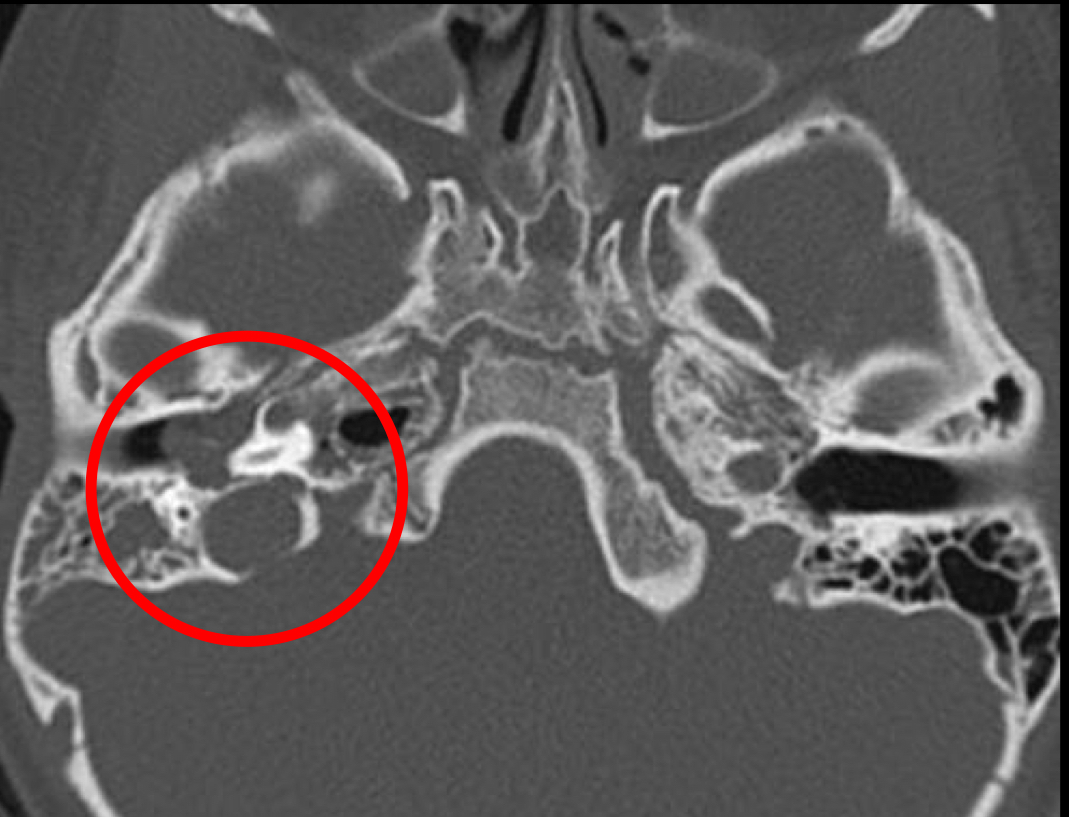

TC Y RM

mismos hallazgos en otitis y mastoiditis

MASA QUE DESTUYE HUESO= SOLO ASI SE DIFERENCIA

RM T2 MEJOR DX BRILLA

RM T2 COLESTEATOMA

BRILLA

MASA QUE DESTRUYE HUESO